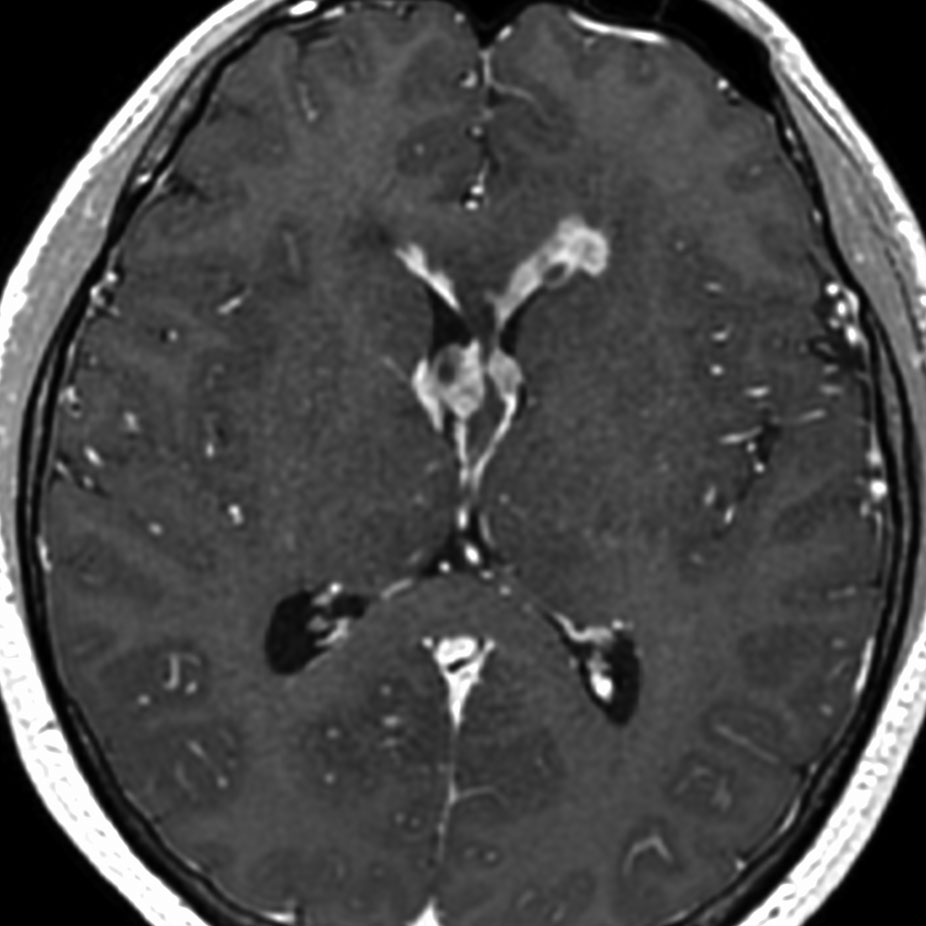

ガドリニウム増強では,前頭葉腫瘍というより,側脳室壁にベトベトくっついているような腫瘍です。germinoma特有のsubependymal infiltration像を示します。

生検後2ヶ月,セカンドオピニオンのために受診された時の画像です。腫瘍が縮小傾向にあります。入院中に行われた何度かのCT被曝の影響で,germinomaの退縮が生じたのだと判断しました。